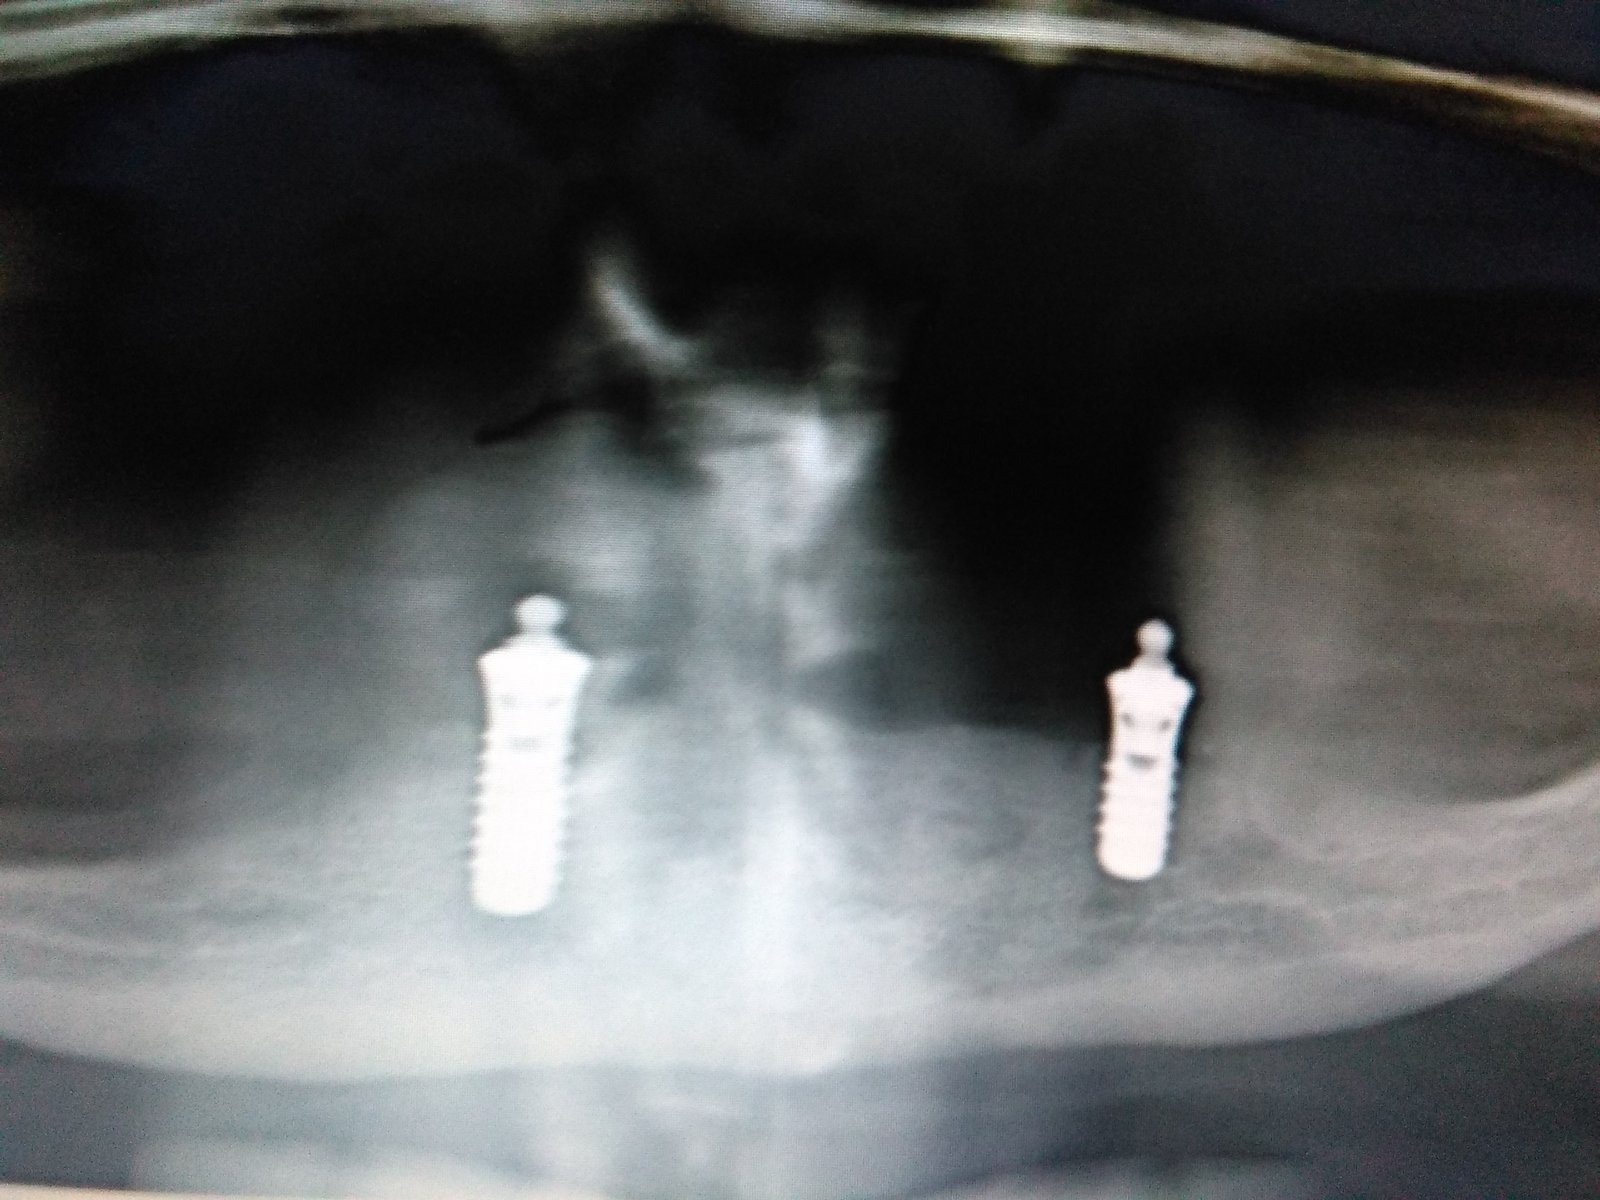

Buenas tardes. Necesito saber que implantes son. La paciente tiene los teflones de la sobredentadura muy gastados. No tiene retención y está muy incómoda. Se los cambiamos hace un par [...]